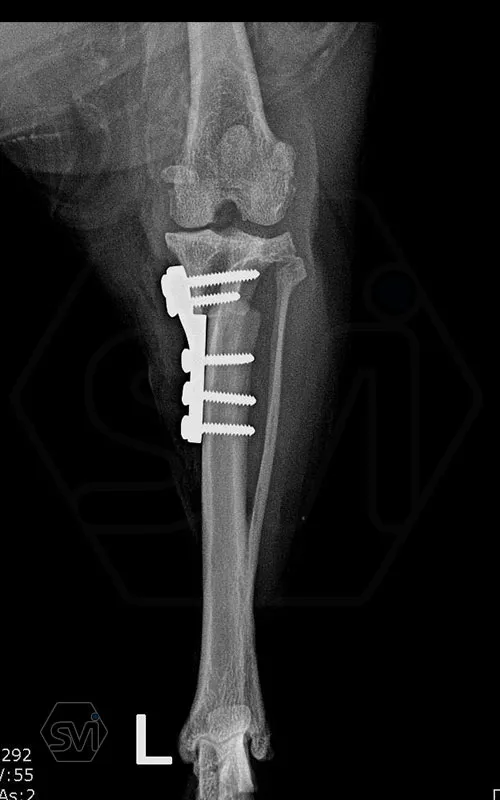

The next step was an osteotomy with a curved saw using an R12 blade and a Smartvet cordless TPLO saw. Since no JIG is used for the operation, the excised bone piece was grasped with a small pointed condylus forceps (small-spitzige) and adjusted to the desired position by the sterile assistant: that an approx. a 2 mm step should be created. This position was fixed with a 1.0 mm K-wire starting from the proximal end of the tuberositas tibiae. The TPLO-M mini plate was used, with a minimal bend, the proximal piece was curved outward for a better fit. The terraced design of the plate was aligned with the 2.2mm step to the bone. Screw insertion order: proximal middle and cranial holes, then distal middle DCP holes (INTRAOP. PICTURE) The three screws were tensioned continuously and alternately, and the temporaly K-wire was removed, thus providing the opportunity for the displacement to be complete and for the osteotomized tibia to assume the position formed by the plate and for compression to develop between bone surfaces. The other screws were then inserted. In our case, the K-wire was no longer returned. (If there is place and way for it, we can put it back a few tenths of a millimeter thicker than the previous one taken out to relieve the crista tibiae. tibiae may break under the load.)

A következő lépés az ívelt fűrésszel való oszteotomia volt, R12 pengét használtunk, és Smartvet akkumlátoros fűrészt. Mivel JIG-et nem használunk a műtéthez, a kivágott csontdarabot kisméretű hegyes condylus-fogóval (kis-spitzige) megragadtuk, és a steril asszisztens a kívánt pozícióba állította: egyrészt a TPA-nak megfelelően elforgatva, majd medialis irányba kiemelve kissé tibia síkjából úgy, hogy egy kb. 2 mm-es lépcső keletkezzen. Ezt a pozíciót egy 1,0 mm -es K szeggel rögzítettük a tuberositas tibiae proximális végétől indítva. A TPLO-M mini lemezt használtuk, egy minimális hajlítással a proximális darabot kifelé görbítettük a jobb illeszkedés végett. A lemez teraszos kialakítását a lépcsőhöz igazítottuk (2,2 mm-es eltolás), és így pozícionáltuk a lemezt. A csavarok behelyezési sorrendje: proximális darab középső és cranialis furat, majd a distalis darab középső DCP furat (INTRAOP. KÉP) A három csavart folyamatosan, felváltva feszítettük, majd a végállapot előtt a pozíciót rögzítő K-szeget a tub. tibiae-ből eltávolítottuk, ezzel biztosítottuk a lehetőségét annak, hogy az eltolás teljes legyen és az oszteotomizált tibia felvegye a lemez által kialakított pozíciót, illetve, hogy kialakuljon a kompresszió csontfelszínek között. A többi csavar behelyezése ezután következett. Esetünkben a K-szeget már nem tettük vissza. (Abban az esetben, ha van hely és mód rá, akkor a kivett előző szegnél néhány tized milliméterrel vastagabbat visszahelyezhetünk a crista tibiae tehermentesítése céljából. Itt ügyelni kell, hogy a szeg soha se menjen a patella egyenes szalagjának tapadási pontja alá, mert a tub. tibiae letörhet a terhelés hatására.)